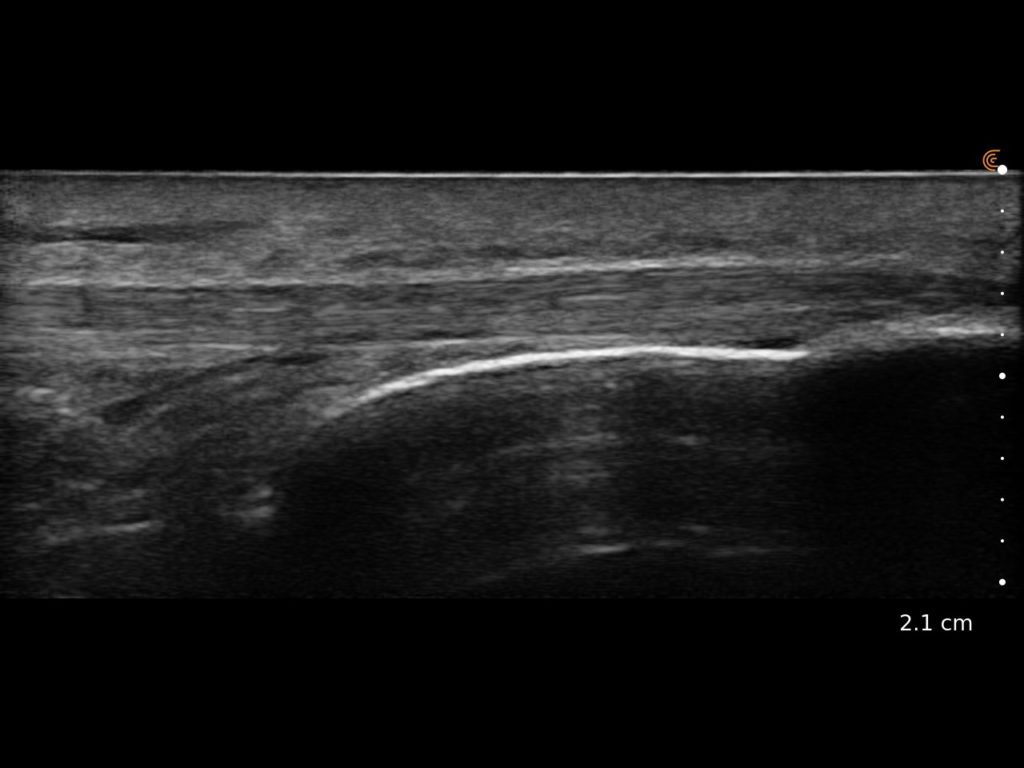

Clarius HD3 is the ideal wireless ultrasound scanner for musculoskeletal (MSK) imaging and procedural guidance. Make a confident diagnosis with high-resolution imaging of muscles, joints, ligaments, tendons, and cartilage both at rest and in motion.

What I like about Clarius is that it is an excellent ultrasound that allows me to have versatility, quality and precision.